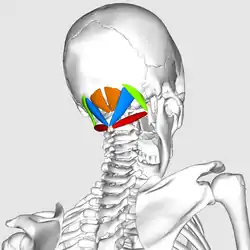

The suboccipital muscles are a group of muscles defined by their location to the occiput. Suboccipital muscles are located below the occipital bone. These are four paired muscles on the underside of the occipital bone; the two straight muscles (rectus) and the two oblique muscles (obliquus).

The muscles are named

- Rectus capitis posterior major goes from the spinous process of the axis (C2) to the occipital bone.

- Rectus capitis posterior minor goes from the middle of the posterior arch of the atlas to the occiput.

- Obliquus capitis superior goes from the transverse process of the atlas to the occiput.

- Obliquus capitis inferior goes from the spine of the axis vertebra to the transverse process of the atlas.

Position of suboccipital muscles. Animation.

Position of suboccipital muscles. Animation. Close up. Seen from below.